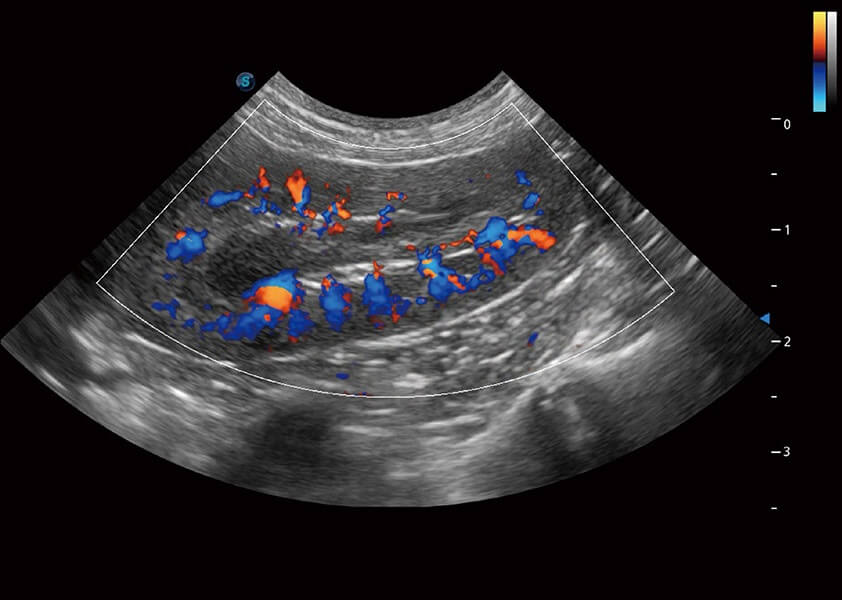

4T血流成像 微察秋毫

融合不同血流成像技术的优势,即可以提升血流成束性,同时可提高血流的视觉敏感性。

PDI 能量多普勒血流

提供高灵敏度和空间分辦率的血流图像,获得更加真实和丰富的诊断信息。

SR Flow 高分辨率血流成像

能够清晰显示细小、低速血流图像,获取传统彩色多普勒技术难以得到的细节和信息。

Micro F 显微血流成像

通过创新的Matrix E自适应滤波器和超长时间域算法,极大提升超低速微细血流的检出能力,同时更精准地滤除软组织和噪声信号,为兽用医生提供以往无法通过常规血流获得的疾病诊断信息。

Bright Flow 立体血流成像

在传统二维血流成像的基础上,呈现血流的立体感,具有动感的生命力之美。精确区分不同血管的空间关系,提高了血流的视觉敏感性。

优异的基础图像

(犬)四腔心血流

(犬)肾脏血流